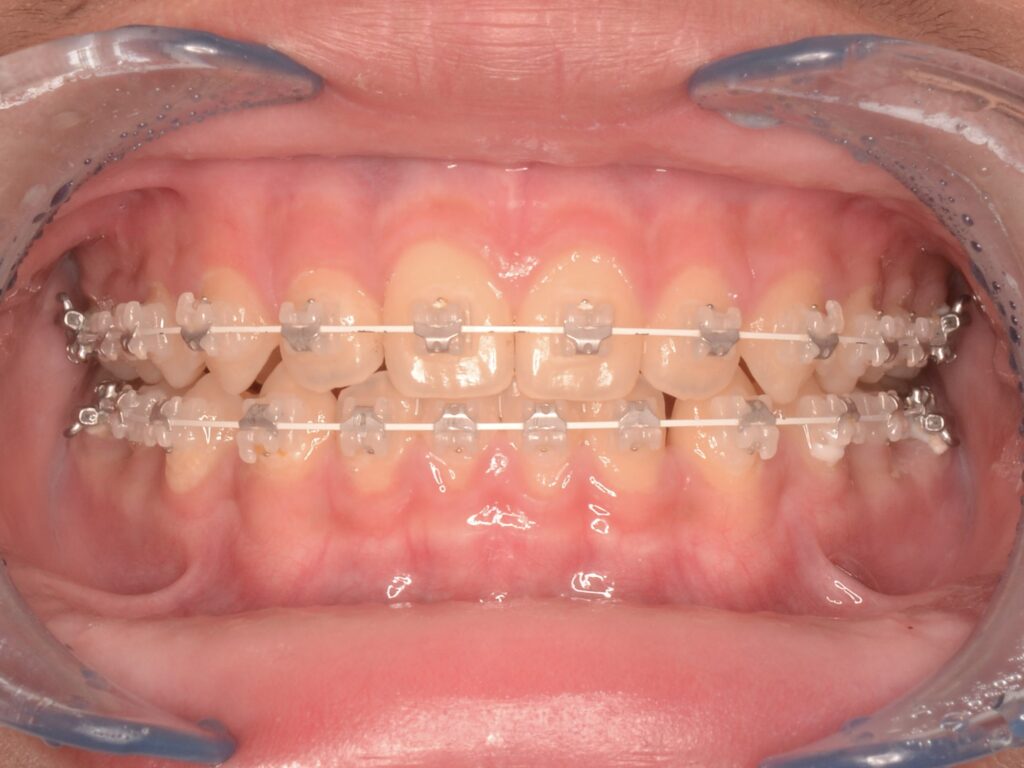

矯正治療の症例